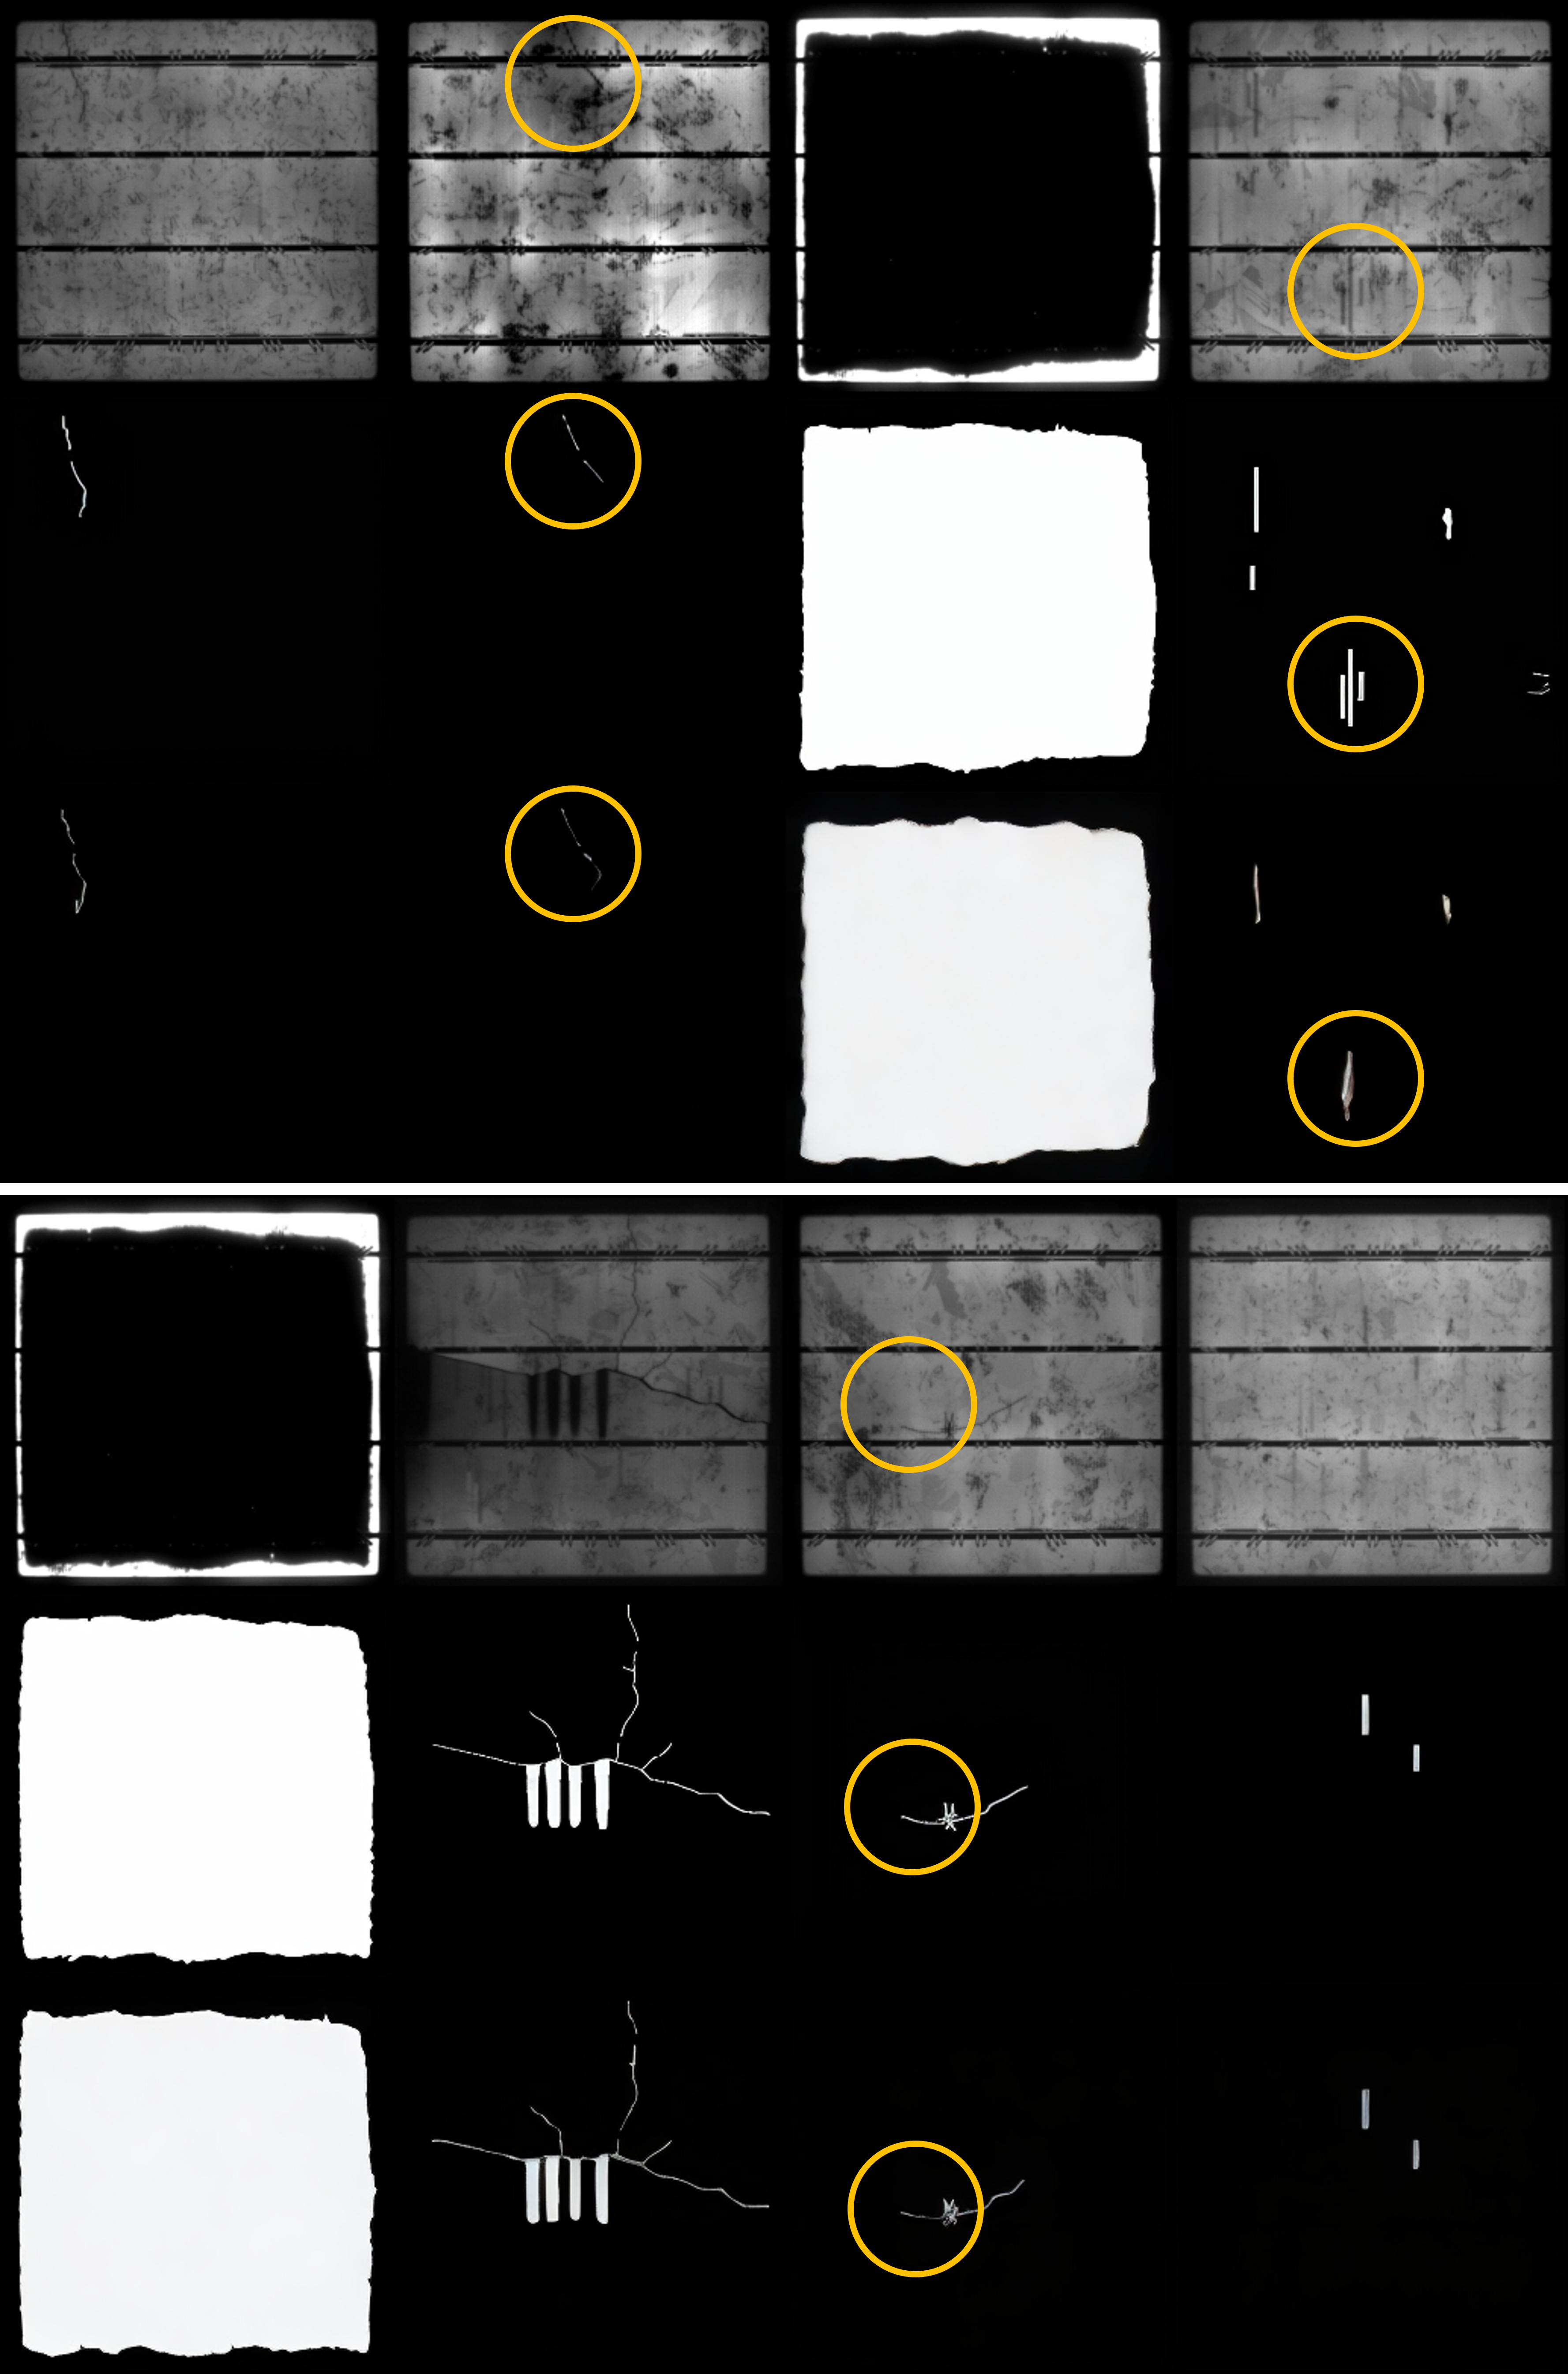

Refer to caption

Figure 2: Visual comparison across three cross-modal tasks: IXI medical conversion, Sentinel SAR-to-optical, and PSCDE semantic mask. (See more in Appendix 6.15).

PSCDE (Semantic Translation): PSCDE requires semantic recovery far beyond the other tasks, and CDTSDE preserves thin and fragmented structures under noise, maintaining mask continuity and topology (clearly see from the PSCDE columns: 2). DOSSR approximates shapes but slightly oversmooths edges, whereas Pix2Pix introduces spatial inconsistencies and over-segmentation. The bridge-based methods DBIM, ABridge, and BBDM struggle to recover fine structures, yielding jagged, disconnected, or artifact-heavy masks, so CDTSDE remains strongest on this dataset.

Industrial Defect Detection On PSCDE, CDTSDE delivers the strongest pixel-level performance and topology preservation, achieving the highest Dice (0.4880.488) and IoU (0.4030.403), the best Skeleton F1 (0.6140.614), and the lowest boundary error by Hausdorff distance (39.8739.87). It also attains the best precision/recall balance (0.784/0.4320.784/0.432), enabling recovery of thin structures under noise. DOSSR is consistently second across all metrics (Dice 0.4600.460, IoU 0.3700.370, Precision 0.6590.659, Recall 0.4130.413, Hausdorff 59.5359.53, Skeleton F1 0.5870.587). In contrast, the bridge-based diffusion methods DBIM, ABridge, and BBDM all lag far behind the top two: DBIM attains moderate region overlap (Dice 0.1670.167, IoU 0.1580.158) and the lowest Hausdorff (101.49101.49) among the bridges but suffers from very poor Skeleton F1 (0.0040.004), while ABridge and BBDM largely fail to produce meaningful semantic translations (Dice 0.024\leq 0.024, IoU 0.012\leq 0.012) and exhibit severe boundary errors (Hausdorff 161.89\geq 161.89). Pix2Pix sits between these extremes, with lower overlap than the proposed methods (Dice 0.1780.178, IoU 0.1730.173) and large boundary deviation (Hausdorff 156.28156.28) alongside weak structural fidelity (Skeleton F1 0.0530.053).